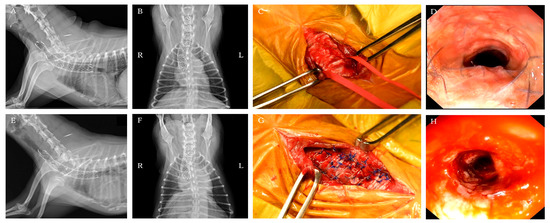

Tracheal stent fracture is a major complication of endoluminal tracheal stent (ELS) for canine tracheal collapse, and optimal management strategies remain unclear. A 4-year-old Yorkshire Terrier presented with respiratory distress caused by complete ELS fracture. Imaging and bronchoscopy revealed intraluminal protrusion of fractured stent segments, ventral tracheal cartilage invagination, and marked luminal deformation. A polypropylene linear prosthesis (PLLP) was selected as an external tracheal support. Its continuous band-like structure allowed broad and uniform reinforcement of the tracheal wall and redistribution of mechanical stress. PLLP placement successfully restored a near-normal tracheal contour and stabilized the fractured stent without introducing additional intraluminal material. Postoperative bronchoscopy confirmed improved tracheal patency, and no further deformation or stent damage was observed despite several months of altered airway dynamics associated with laryngeal paralysis. This case suggests that PLLP may represent a valid surgical option for managing tracheal stent fracture in dogs. Full article

Figure 1